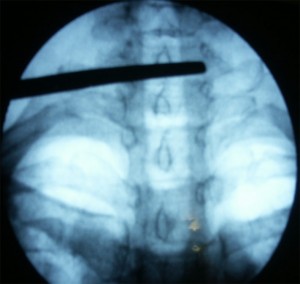

Con el paciente en decúbito prono con la cabeza en posición neutra y los brazos en dirección caudal se coloca el arco de fluoroscopia en posición anteroposterior y se localiza el espacio interlaminar seleccionado con ayuda de un marcador radiopaco. Se debe conseguir que las apófisis espinosas estén equidistantes entre los pedículos y que no exista un doble contorno en los cuerpos vertebrales. Para eliminar el doble contorno si existiera se debe de realizar u movimiento del arco de fluoroscopia en  dirección craneocaudal hasta que desaparezca. No se recomienda la punción en línea media por encima de C5 debido a la elevada incidencia de no fusión del ligamento amarillo. Una vez marcado el lugar de punción se inserta la aguja de Tuohy en visión túnel y dirección al punto diana, la entrada al espacio epidural se realiza  con la técnica de pérdida de resistencia. La técnica se puede realizar con suero, aire y gota pendiente. La elección de la técnica dependerá del entrenamiento de cada profesional con cada una de ellas. Cuando se alcanza el ligamento interespinoso, se rota el arco a posición lateral, para comprobar la profundidda de la aguja y minimizar el riesgo de punción dural. Como la visión lateral a nivel cervical es muy dificultosa por la superposición de las imágenes de los hombros, se utilizan proyecciones oblicuas y en esta posición la punta de la aguja no debe sobrepasar el borde anterior de la apófisis espinosa. Una vez localizado el espacio epidural se inyecta de 1-3ml de contraste radiopaco en tiempo real verificando la posición de la aguja y asegurándonos de que no nos encontramos en el interior de un vaso. Comprobamos nuevamente la distribución del contraste con el arco en posición anteroposterior visualizando el epidurograma y administramos un corticoide no particulado con el anestésico local. Finalmente se retira la aguja con el mandril.